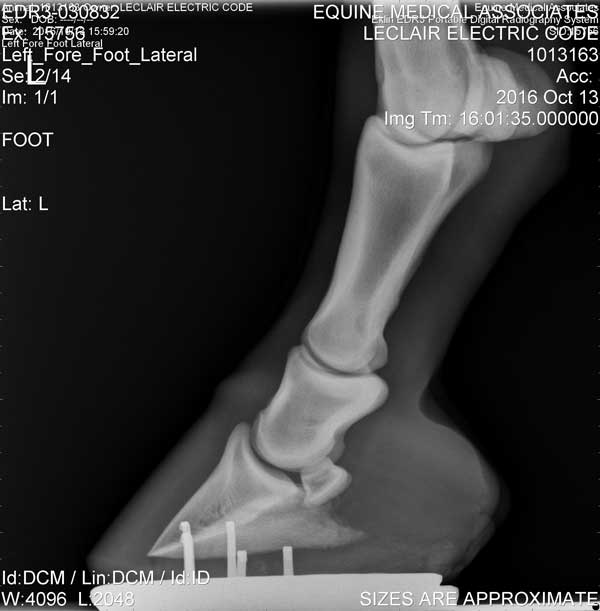

Hoof

Left